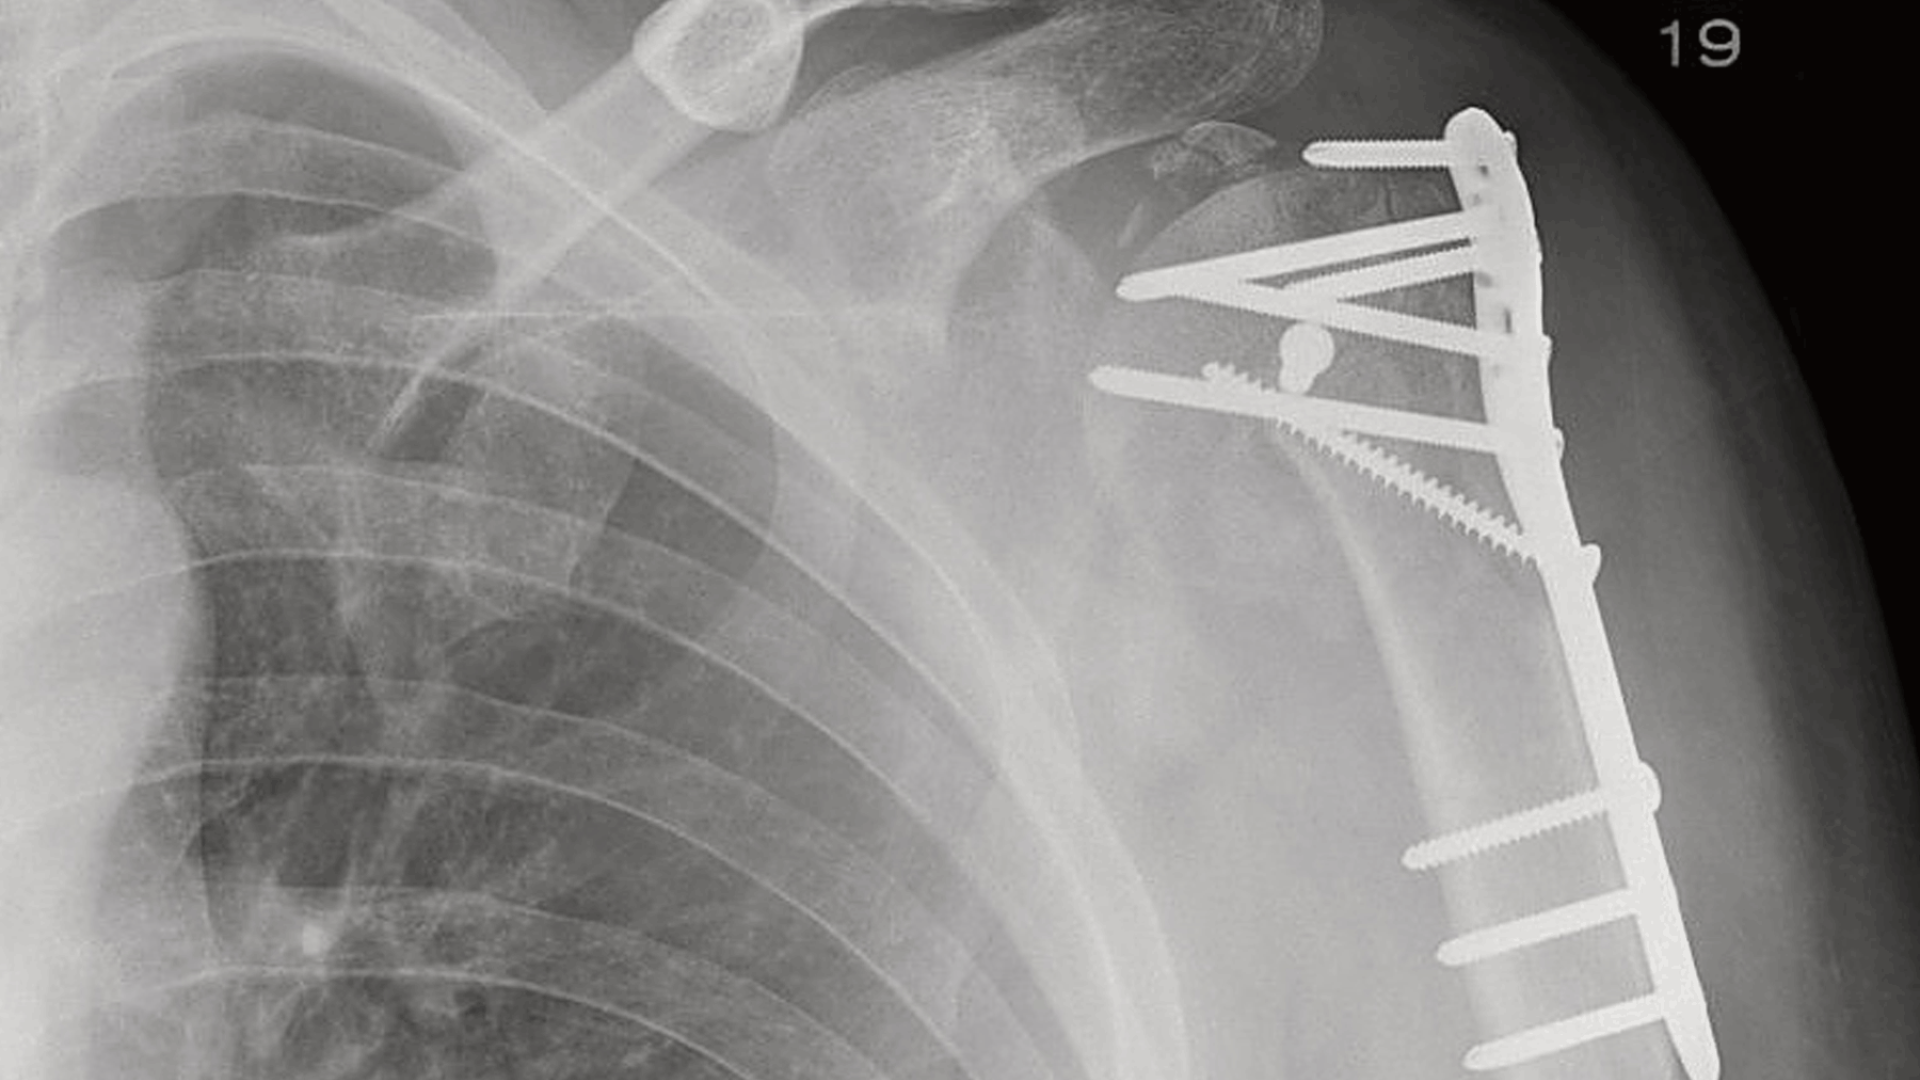

Metallisten luurikkojen korjaukseen käytettyjen osien ja ruuvien hyvä puoli on niiden hinta ja yksinkertaisuus, mutta ne pitää poistaa luun parannuttua. Tämä tarkoittaa potilaalle toista, ikävää leikkausta kaikkine harmeineen. Biologisesti luussa hajoavat polymeerikappaleet puolestaan ovat kalliimpia ja niiden asentaminen on yleensä työläämpää sekä vaatii enemmän ainetta luun sisälle ja ympärille. Niistä tulee myäs helpommin tulehduksia.